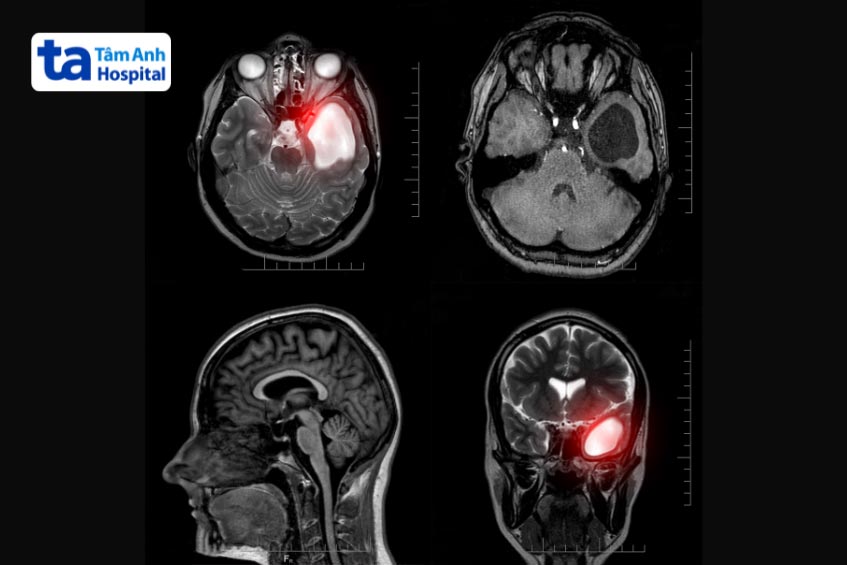

U góc cầu tiểu não (Cerebellopontine angle (CPA) tumors) là khối u lành tính, nằm ngoài trục, mọc lên trong khoang dịch não tủy, được giới hạn bởi cầu não, bán cầu tiểu não và đỉnh xương đá.

Để chẩn đoán u ở góc cầu tiểu não, bác sĩ có thể chỉ định thực hiện các xét nghiệm chuyên sâu, gồm:

Đơn cử, Bệnh viện Đa khoa Tâm Anh có nhiều máy móc, thiết bị hiện đại, tân tiến, phục vụ tối ưu cho quá trình chẩn đoán, điều trị, phẫu thuật như: Robot AI Modus V Synaptive, bộ đôi định vị dẫn đường thần kinh AI Neuro-Navigation Curve, BrainLAB và kính vi phẫu AI K.Zeiss Kinevo 900, máy CT 768 lát cắt, CT 1975 lát cắt, CT 100,000 lát cắt, MRI 1,5 – 3 tesla…

Nhờ sự hỗ trợ đắc lực của các “siêu máy” cùng kinh nghiệm chuyên sâu của bác sĩ, hàng nghìn trường hợp mắc bệnh lý thần kinh, trong đó có bệnh u góc cầu tiểu não đã được điều trị thành công, ít biến chứng, sớm phục hồi chức năng và hạn chế nguy cơ tái phát.